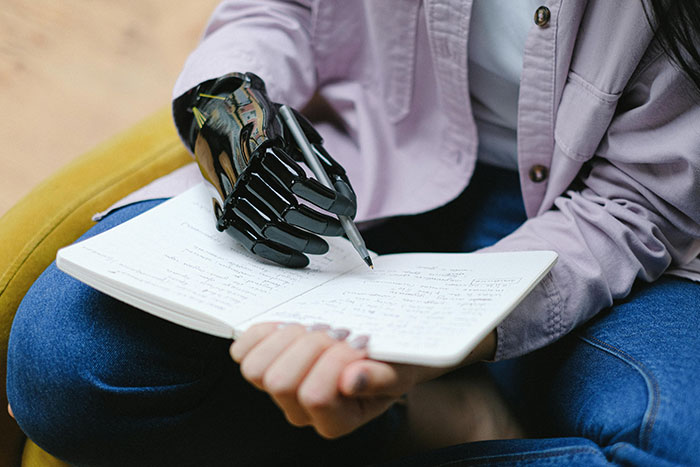

80% of amputations are due to diabetes.

Watch your health, people.

Image credits: 314159265358979326